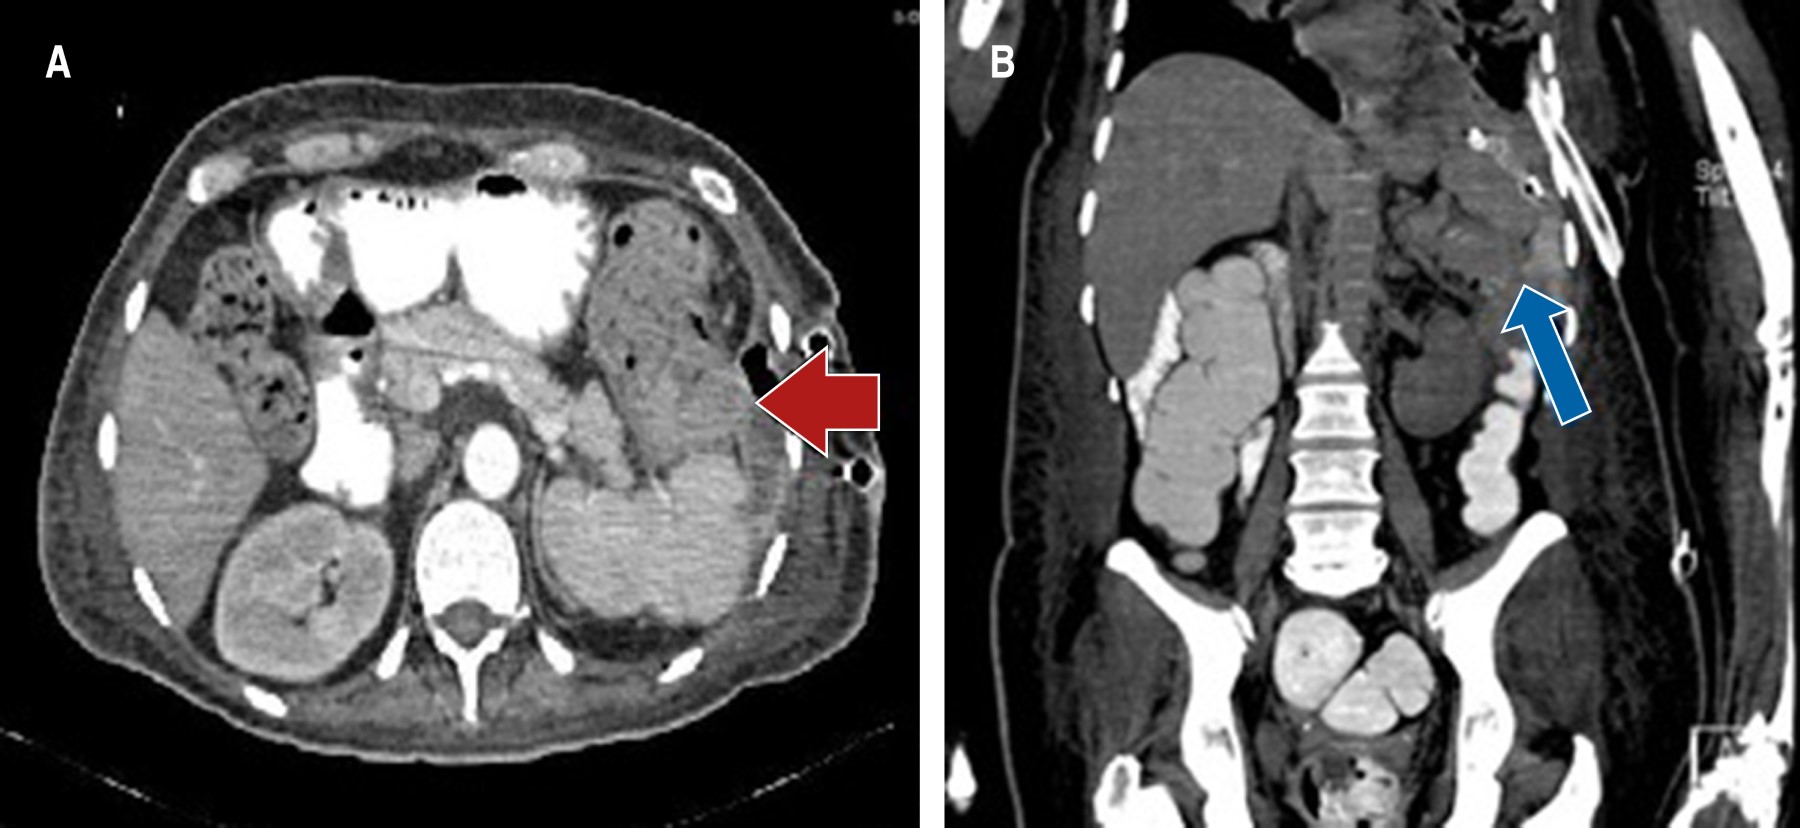

En su evolución posoperatoria con adecuada expansión pulmonar (Figura 2), a las 72 horas presentó salida de material fecaloide por sondas endopleurales, por lo cual se realizó tomografía toracoabdominal doble contrastada por la sospecha de fístula de colon, la cual se documentó con el paso de medio de contraste a cavidad torácica y aire proveniente del colon (Figura 3). El cultivo del líquido pleural fue de Escherichia coli, por lo que se inició manejo con meropenem.

Se programó paciente para laparotomía exploratoria donde se encontró absceso subfrénico de 200 cm3, el cual se drenó. Se observó tumor dependiente de ángulo esplénico de colon de 10 por 12 cm, fistulizado hacia cavidad torácica (Figura 4). Se realizó hemicolectomía izquierda con colostomía en bolsa de Hartmann y colocación de drenaje. El diagnóstico de la pieza quirúrgica fue de adenocarcinoma moderadamente diferenciado, ulcerado y perforado que invade todas las capas de la pared con infiltración vascular y linfática.